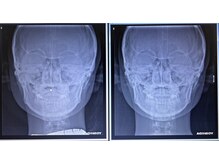

業界歴26年と施術10万人超実績の院長!カイロ日本一(H16/12月/日本カイロ連合会調査)独自で考案しTVでも紹介された河野式小顔輪郭矯正は、海外でも高い評価を受け、頭蓋骨と顔骨格22個にアプローチし、顔の左右バランを整え、骨格から小顔にします!旭川店は数日の営業。ご予約希望の方はLINE【ID:kogao22_kouno]まで。